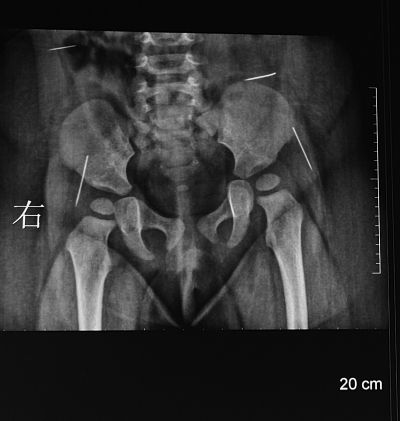

X片显示,萌萌体内有四根针状金属物。 X片显示,萌萌体内有四根针状金属物。

陈医生告诉记者,看着襁褓里哭闹不已的女婴,他首先对女婴进行初步检查,发现她的臀部有一明显的针眼,而且有点感染,后经女婴父母介绍他才得知,7月22日,由于萌萌一直哭闹,家人在她的臀部发现一根没有针鼻的缝衣针,于是送到淮安市第一人民医院将这根冒出体外的缝衣针给拔掉了,该院也为女婴拍了一次X片,X片显示女婴体内还有四根针状金属物,医院建议到妇幼保健院做手术。

“有一点是肯定的,这四根缝衣针都是通过外力作用被戳进萌萌体内的”,陈卫兵告诉记者,从取出的缝衣针所附的体液颜色以及缝衣针所处体内位置的感染程度来看,这四根缝衣针在萌萌体内至少一个多月了。在萌萌手术前所拍的CT片上,清晰可见四个白亮亮长短不一的缝衣针,所处的位置分别在腰部和臀部两侧。陈卫兵告诉记者,臀部的两根缝衣针非常危险,已经移动到髋关节之间,有可能触及萌萌的坐骨神经,处于腰部的那根更危险,因为眼看着就要移动到肝脏位置。

昨天早晨8点30分,萌萌被推进手术室,到中午12点40分,医生将其体内四根没有针鼻的缝衣针全部取出。“整个手术可以说是惊心动魄,真的像大海捞针”,为萌萌主刀的陈卫兵向记者介绍,该手术要对萌萌进行全麻,但萌萌还小,最后选择用呼吸式麻醉对其全麻,骨科等科室的医生也被请到手术室一起为萌萌做手术,整个手术最难的还是要准确定位萌萌体内的四根缝衣针。在手术室里,他一边看着放射科所拍的X片,了解萌萌体内的缝衣针大概位置,一边用电话与放射科主任联系,通过早晨刚拍的CT片来准确定位缝衣针的位置。

在放射科,记者看到了萌萌手术前所拍的CT片,放射科主任鸥继华指着一张能看出缝衣针在萌萌体内一运动轨迹的片子告诉记者,这根缝衣针现在所处的位置已在接近臀部的髋关节,从运动轨迹来看,不排除是人为地从上往下戳进去的,而且取出的四根都没有针鼻,如果真的是人为的,那戳针的人还很有心计,因为如果不把针鼻去掉,那么整根缝衣针戳进皮肤后,由于针鼻有个小孔会造成缝衣针在进入萌萌体内时造成一定的阻力,缝衣针也就不会很快进入体内。四根缝衣针入体运动轨迹周围的软组织都已受感染。鸥主任告诉记者,他从事这么多年的放射工作,在一个人的体内,尤其是11个月大女婴的体内发现四根缝衣针还是头一次。